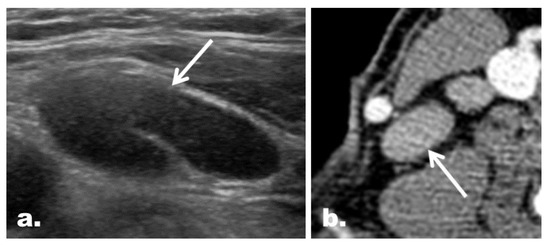

2.5. CT Imaging Features in the Reclassified Cases